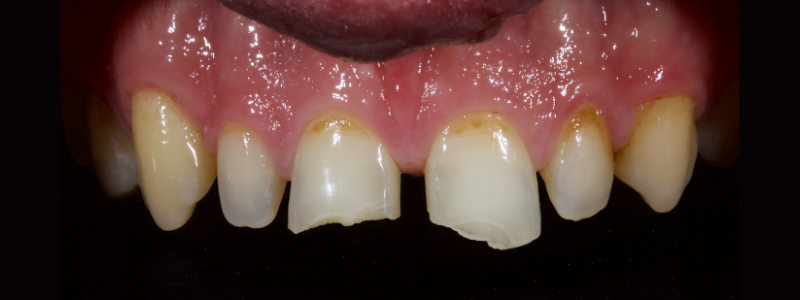

To illustrate this protocol, we will explore the case of a 55-year-old female patient — a dentist — with esthetic and functional concerns as well as moderate to advanced tooth surface loss (TSL).

The anterior teeth had lost around 25% of the coronal structure, and dentin was exposed (Figs. 1–3). The patient requested a minimally invasive solution.

In this case, a 23-year-old male presented with Ellis Class II fractures of both central incisors (Fig. 23). He had no interest in closing his diastema or restoring the peg laterals. A treatment plan was agreed upon to restore both central incisors with direct resin.